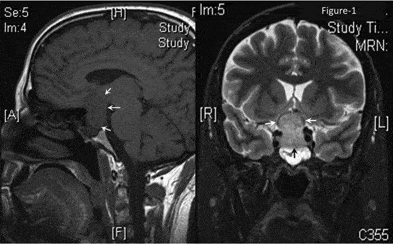

- दिमाग का CT-स्कैन

- पिट्यूटरी MRI

अगर हाइपोपिटिटारिज्म का कारण ट्यूमर है तो आपको इस ट्यूमर को दूर करने के लिए सर्जरी की जरूरत हो सकती है ताकि ट्यूमर को निकाला जा सकते। इसके साथ ही रेडिएशन थेरेपी की भी जरूरत पड़ सकती है।